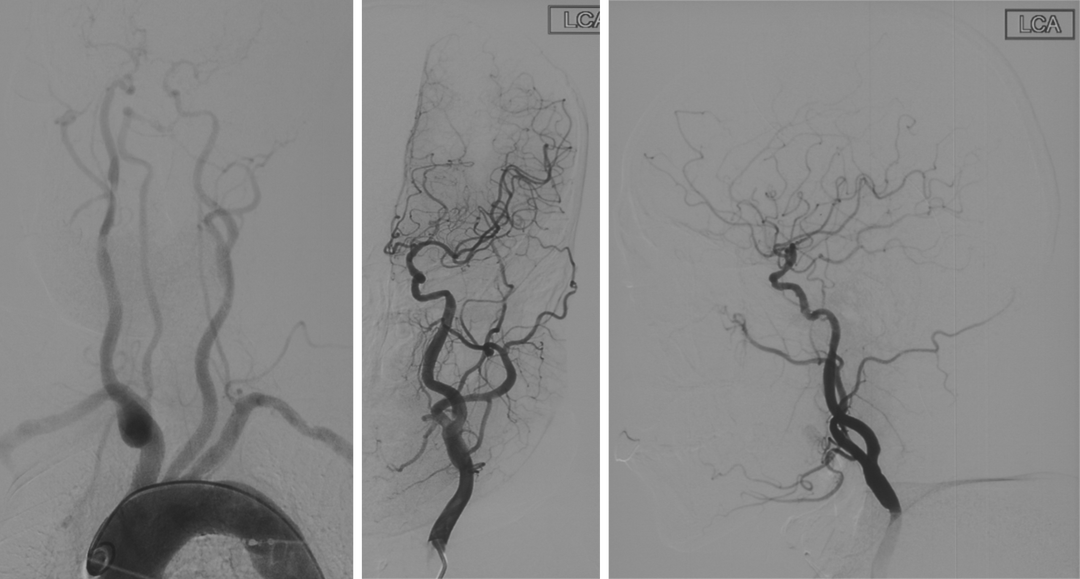

辅助检查(DSA)

主动脉弓+L-CA

波科支架怎么样径技-弓上病例大赏|第210期·右侧颈内动脉球囊扩张术+支架植入术_https://www.jmylbn.com_新闻资讯_第11张

R-CA

波科支架怎么样径技-弓上病例大赏|第210期·右侧颈内动脉球囊扩张术+支架植入术_https://www.jmylbn.com_新闻资讯_第12张

VA

波科支架怎么样径技-弓上病例大赏|第210期·右侧颈内动脉球囊扩张术+支架植入术_https://www.jmylbn.com_新闻资讯_第13张